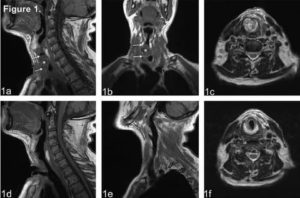

Исследование гортани проводится в положении больного человека лежа на спине. Специалисты, используя различные импульсные последовательности, получают изображения участка дыхательной системы в нескольких плоскостях: сагиттальной, фронтальной, аксиальной.